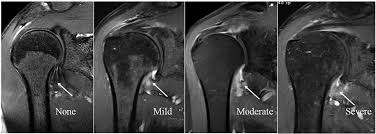

진료실에서 진단은 주로 병력과 X-ray, bone scan, arthrogram, MRI 등으로 시행하게 됩니다. 관절낭에 문제가 생기는 것이기 때문에 단순 엑스레이 촬영에서는 변화가 없을 수 있습니다. Bone Scan 에서 양성이 나온 경우는 스테로이드 주사 치료를 시행해 볼 수 있습니다. 관절낭에 조영물질을 넣어서 엑스레이나 다른 영상을 촬영해 볼 수도 있는데, 유착성 관절낭염의 경우 액와 주머니가 매우 두꺼워져있고, 관절액을 담을 수 있는 공간이 줄어, 일반 견관절 조영술에서 28~35ml 정도의 관절액이 10ml 이하로 줄게 됩니다.

MRI 상에서는 관절낭의 두께가 4mm 이상이 되고, axillary fold의 용량이 감소된 것을 확인해서 진단합니다.